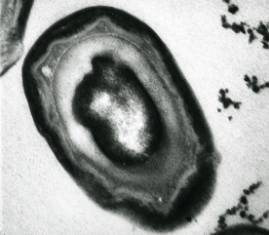

Photo of a fish tuberculosis spore

A close relative of the microorganism that causes tuberculosis in

humans has been found to form spores. This is a sensational finding

because researchers have long been convinced that these kinds of

bacteria — mycobacteria — were incapable of forming spores.